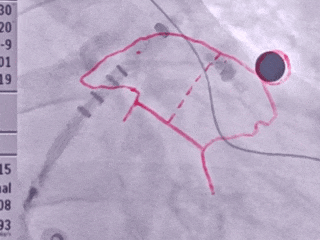

术中DSA左心耳造影

肝位左心耳造影

右肩位左心耳造影

-

心耳呈反鸡翅,穿刺位置偏下偏前

本病例为反鸡翅型左心耳,术中穿刺点需靠下靠前,封堵器输送过程中须确保封堵器输送鞘轴向与左心耳轴向一致,鞘管轴向走向上叶,轴向进行锚定确保封堵器锚定于心耳上缘。